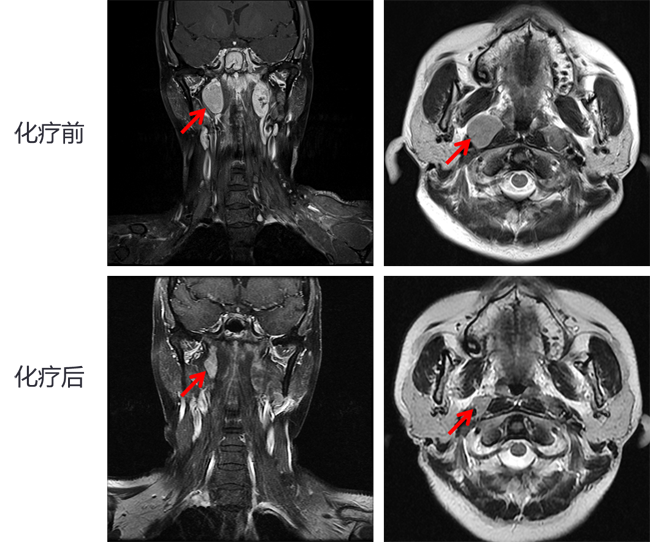

病例示意图:化疗后肿瘤明显缩小